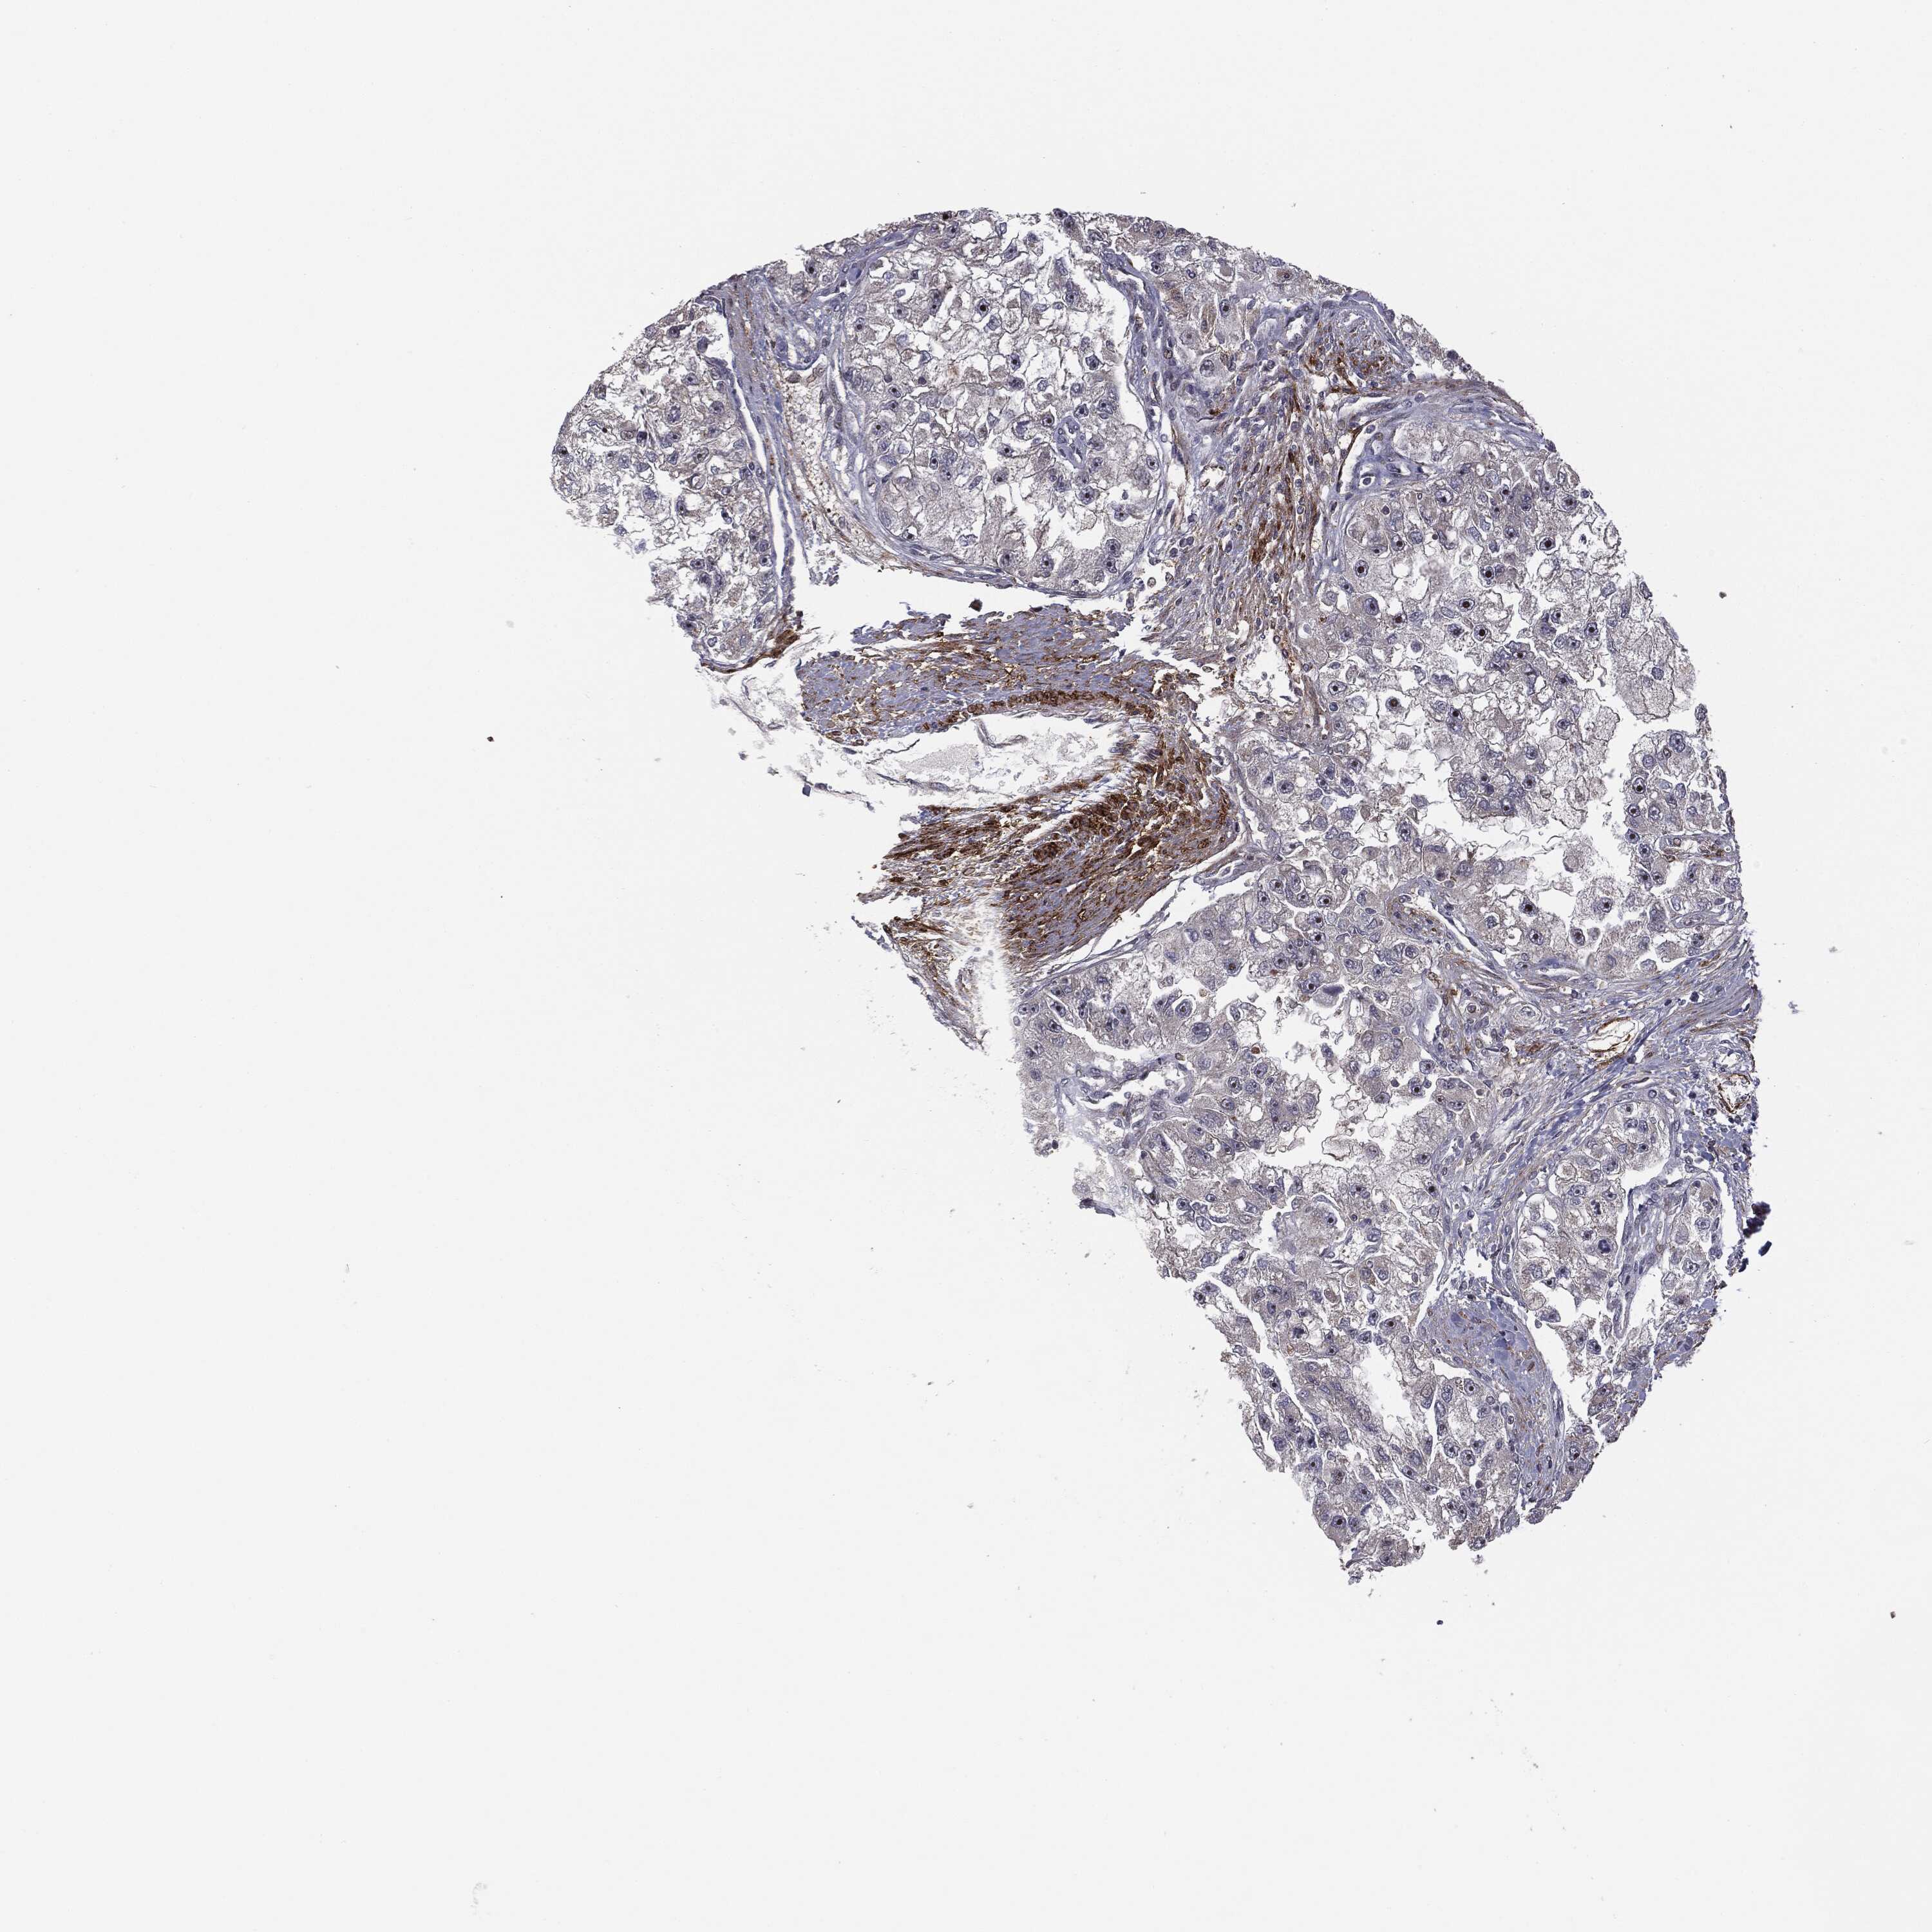

KIDNEY RENAL CLEAR CELL CARCINOMA (VALIDATION) - Interactive survival scatter ploti

The Survival Scatter plot shows the clinical status (i.e. dead or alive) for all individuals in the patient cohort, based on the same data that underlies the corresponding Kaplan-Meier plots. Patients that are alive at last time for follow-up are shown in blue and patients who have died during the study are shown in red.

The x-axis shows the expression levels (FPKM) of the investigated gene in the tumor tissue at the time of diagnosis. The y-axis shows the follow-up time after diagnosis (years). Both axes are complimented with kernel density curves demonstrating the data density over the axes. The top density plot shows the expression levels (FPKM) distribution among dead (red) and alive patients (blue). The right density plot shows the data density of the survived years of dead patients with high and low expression levels respectively, stratified using the cutoff indicated by the vertical dashed line through the Survival Scatter plot. This cutoff is automatically defined based on the FPKM cutoff that minimizes the p-score. The cutoff can be changed by dragging the vertical line or by entering a cutoff value in the square labeled "Current cut-off".

Under the Survival Scatter plot the p-score landscape (black curve; left axis) is shown together with dead median separation (red curve; right axis). Dead median separation is the difference in median mRNA expression between patients who have died with high and low expression, respectively. It is calculated as follows: median FPKM expression of dead patients with high expression - median FPKM expression of dead patients with low expression. This is intended to aid the user in visually exploring custom cutoffs and the associated p-scores and dead median separation.

Individual patient data is displayed and can be filtered by clicking on one or more of the category buttons on the top of the page. Categories describing expression level and patient information include: high, low, alive, dead, female, male and tumor stages. The scale of the x-axis can be toggled between linear and log-scale by clicking on the "x log" button. Mouse-over function shows TCGA ID, patient information and mRNA expression (FPKM) for each patient.

& Survival analysisi

Kaplan-Meier plots summarize results from analysis of correlation between mRNA expression level and patient survival. Patients were divided based on level of expression into one of the two groups "low" (under cut off) or "high" (over cut off). X-axis shows time for survival (years) and y-axis shows the probability of survival, where 1.0 corresponds to 100 percent.

PTEN is not prognostic in Kidney Renal Clear Cell Carcinoma (validation)

Best expression cut offi

Based on the FPKM value of each gene, patients were classified into two groups and association between prognosis (survival) and gene expression (FPKM) was examined. The best expression cut-off refers the FPKM value that yields maximal difference with regard to survival between the two groups at the lowest log-rank P-value. Best expression cut-off was selected based on survival analysis .

When clicking on this number, the vertical dashed line indicating cut-off, the interactive survival plot, and the Kaplan-Meier curve will be adjusted to show results based on the best expression cut-off.

: 26.73

TCGA RNA samplesi

RNA-seq data is reported as average FPKM (number Fragments Per Kilobase of exon per Million reads), generated by the The Cancer Genome Atlas (TCGA) .

Normal distribution across the dataset is visualized with box plots, shown as median and 25th and 75th percentiles. Points are displayed as outliers if they are above or below 1.5 times the interquartile range. FPKM values of the individual samples are presented next to the box plot.

Average pTPM 23.7

Number of samples 100